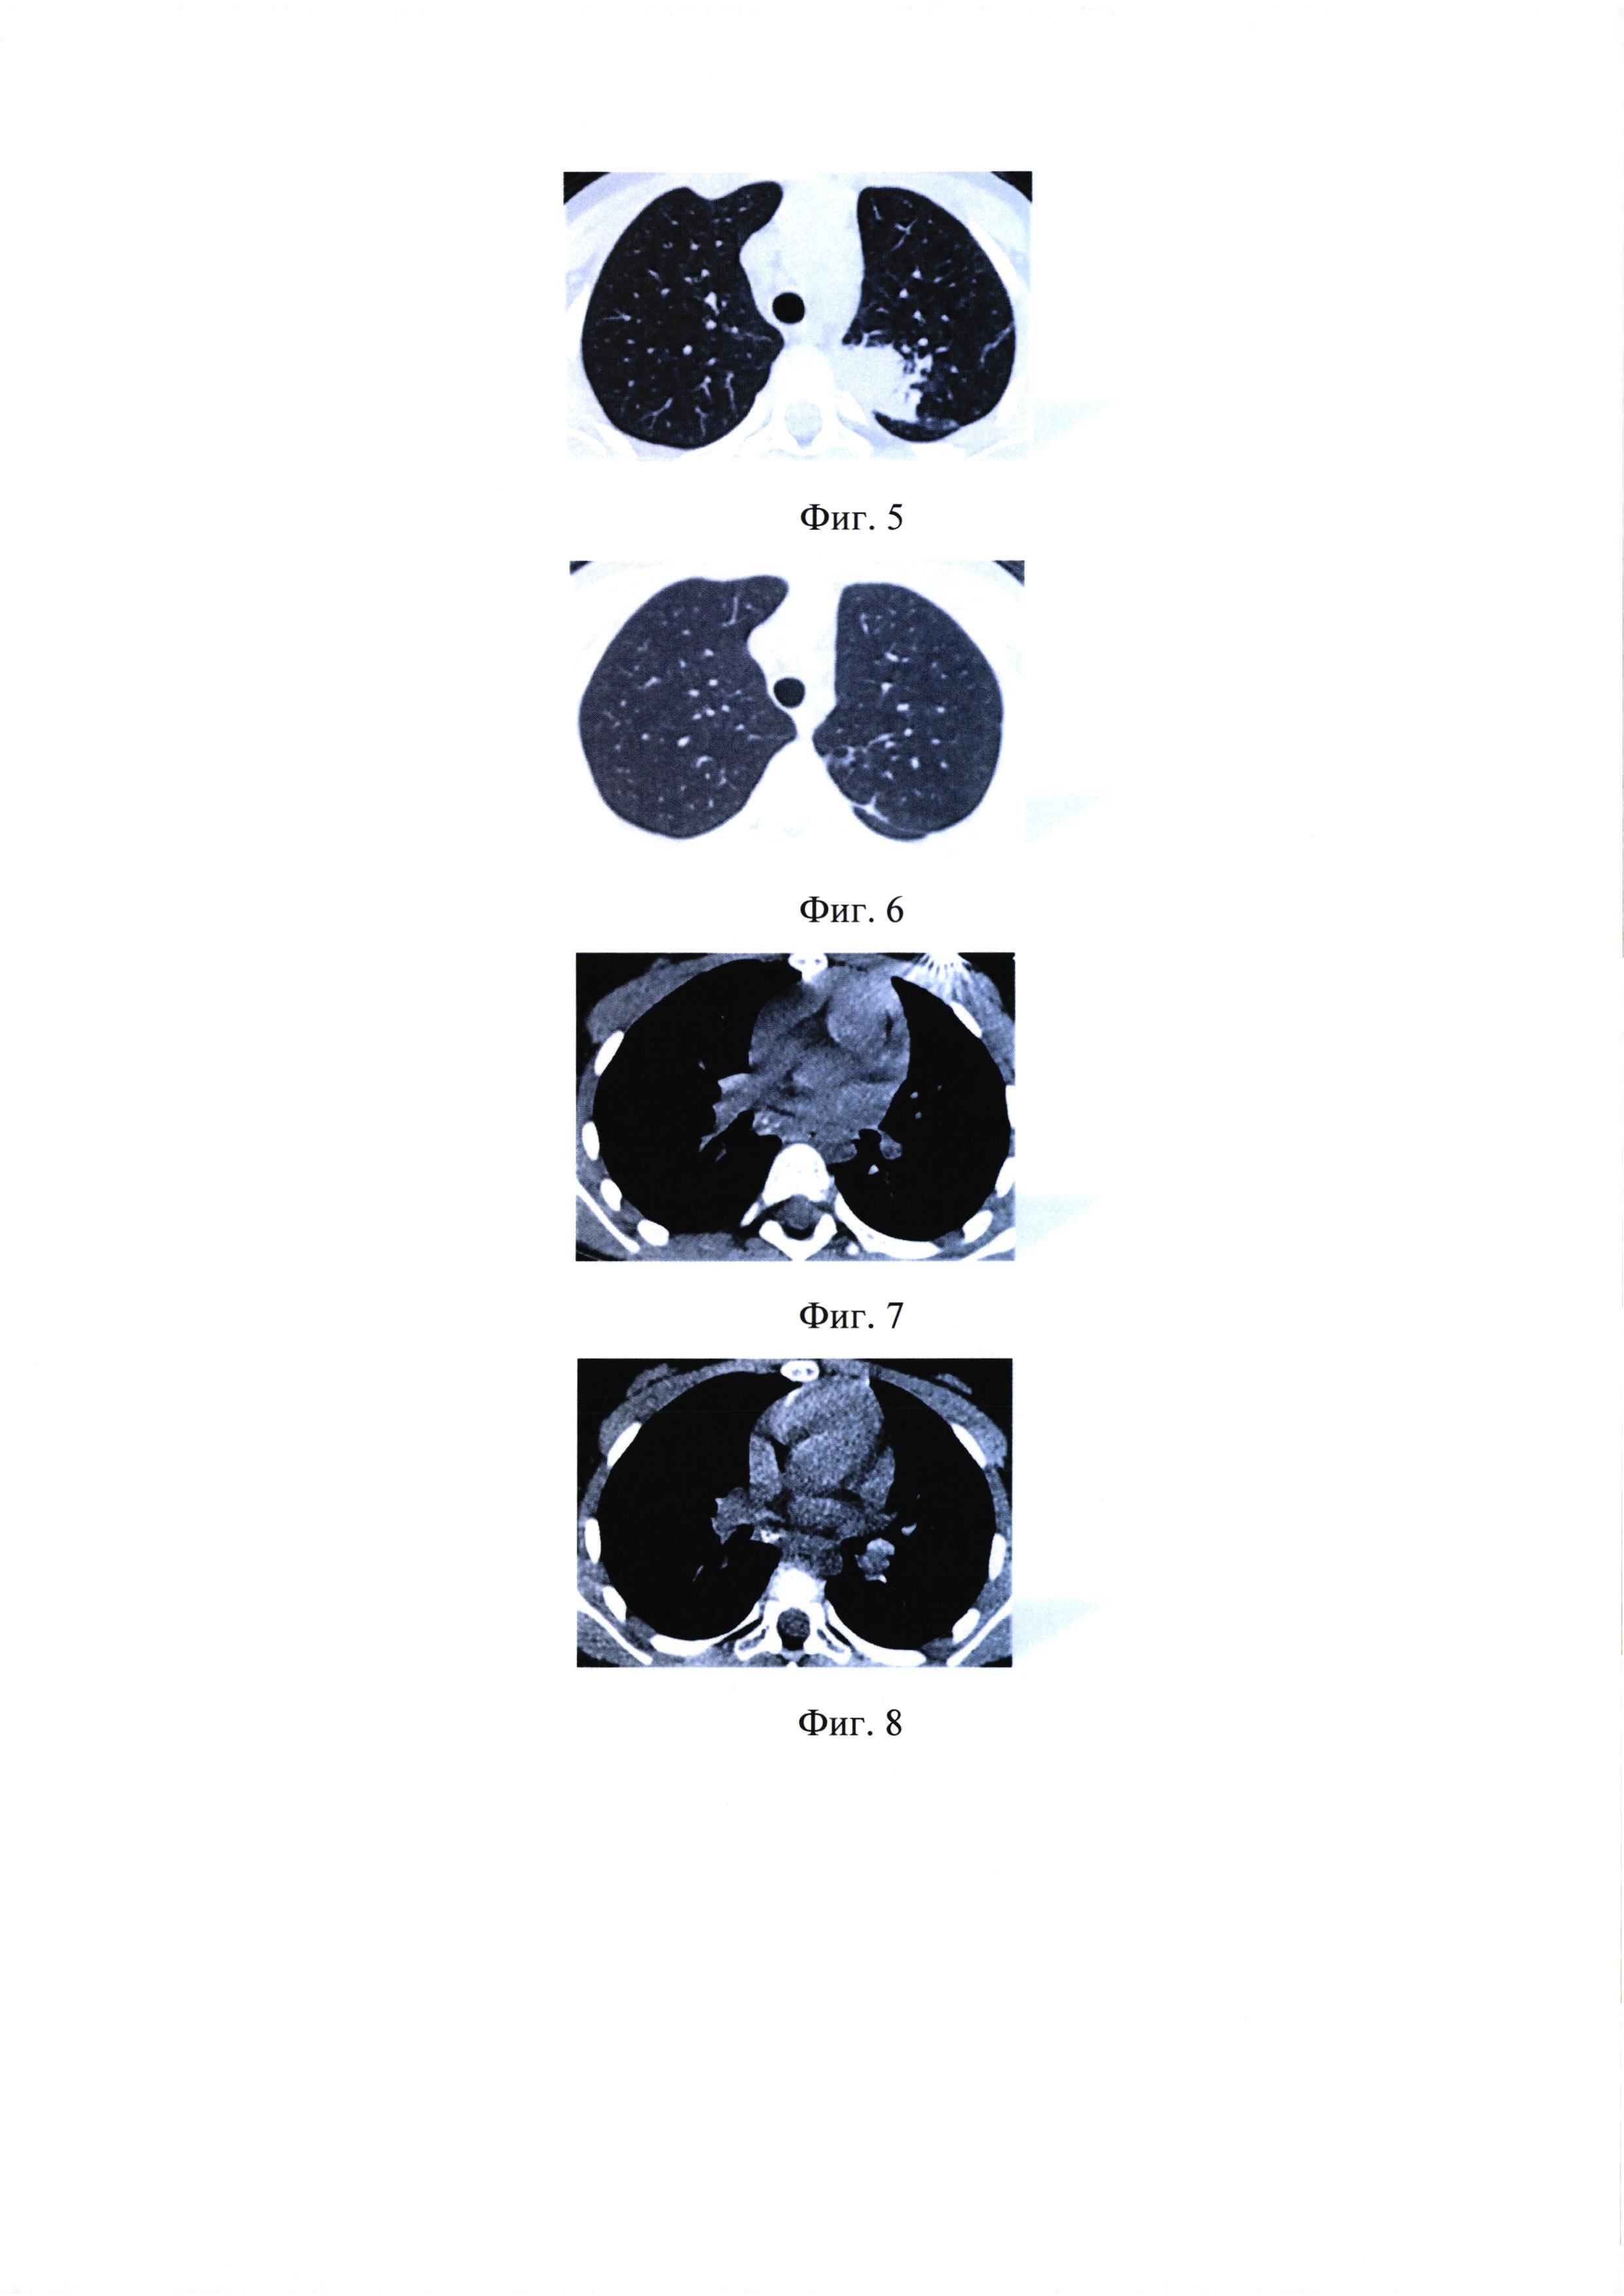

на фиг. 5 - КТ ОГК пациентки У., 8 лет, до начала лечения;

[40]

на фиг. 6 - КТ ОГК пациентки У., 8 лет, через 12 мес. химиотерапии;

[41]

на фиг. 7 - КТ ОГК пациентки М., 5 лет до начала лечения;

[42]

на фиг. 8 - КТ ОГК пациентки М., 5 лет, через 6 мес. химиотерапии;

[43]

Пример 3. Пациентка У., 8 лет. Диагноз: Первичный туберкулезный комплекс верхней доли левого легкого в фазе инфильтрации, уплотнения и начинающейся кальцинации, МБТ (-). Манифестация заболевания под «маской» неспецифической пневмонии. В связи с отсутствием положительного эффекта от приема антибиотиков широкого спектра действия в течение 10 дней была переведена в туберкулезный стационар для дообследования. При сборе эпидемического анамнеза установлен эпизодический контакт с другом семьи, больным туберкулезом с МЛУ МБТ (устойчивость HR). Химиотерапия проводилась по индивидуализированному режиму в связи с осложненным течением туберкулезного процесса у ребенка. В комбинации использовали лекарственные препараты, к которым была сохранена чувствительность МБТ у источника инфекции. Интенсивная фаза 6 ПТП (3 мес. - ZEAmPtoPASFq; 3 мес. - ZEPtoPASFqTzd) в течение 6 мес., фаза продолжения 4 ПТП (ZEPtoPAS) в течение 6 мес., общий срок химиотерапии - 15 мес. Переносимость препаратов удовлетворительная. Течение процесса гладкое. Нормализация гемограммы через 4 мес,. купирование симптомов интоксикации через 6 мес.лечения. По данным КТ ОГК выраженная положительная динамика в виде полного рассасывания туберкулезных изменений в верхней доле левого легкого отмечена через 12 мес. химиотерапии (см. фиг. 5 и фиг. 6).

Пример 4. Пациентка М., 5 лет. Диагноз: Туберкулез внутригрудных лимфатических узлов правой бронхопульмональной и бифуркационной групп в фазе начинающейся кальцинации, МБТ (-). Заболевание выявлено при обследовании по контакту с матерью, больной диссеминированным туберкулезом легких с бактериовыделением с МЛУ МБТ (устойчивость HRSE). Учитывая ограниченный объем поражения (две группы внутригрудных лимфатических узлов), фазу процесса (начинающаяся кальцинация), лечение проводилось по индивидуализированному режиму. Интенсивная фаза 4 ПТП (2 мес. - ZAmPtoPAS; 2 мес. - ZPtoPASFq) в течение 4 мес., фаза продолжения 3 ПТП (ZPtoPAS) в течение 5 мес., общий срок химиотерапии - 9 месяцев. Переносимость препаратов удовлетворительная. Купирование симптомов интоксикации через 3 мес. лечения. По данным КТ ОГК выраженная положительная динамика в виде нарастания кальцинации во внутригрудных лимфатических узлах отмечена через 6 мес. химиотерапии (см. фиг. 7 и фиг. 8).